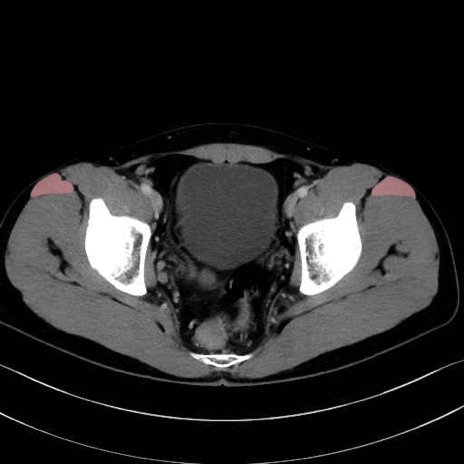

大腿筋膜張筋 (Tensor fasciae latae)